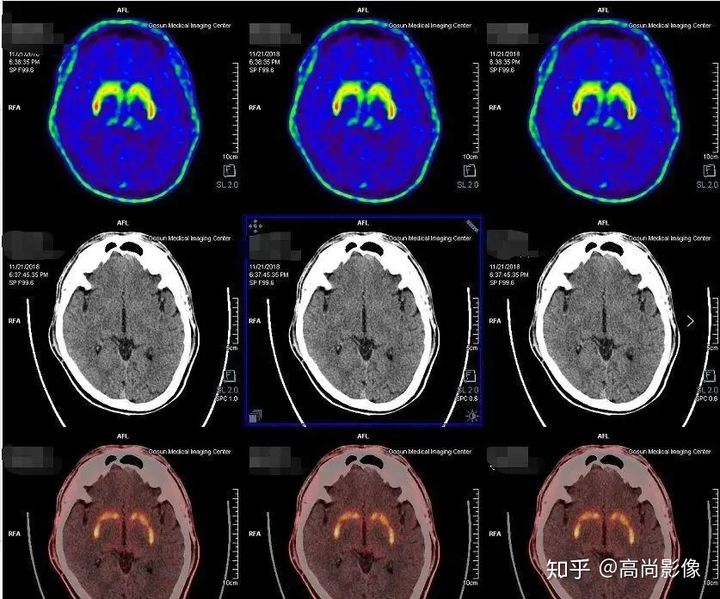

局部18F-FDG代謝顯像主要應(yīng)用于無創(chuàng)定位癲癇病灶。

在國際上,18F-FDG代謝顯像是無創(chuàng)定位癲癇病灶的標(biāo)準(zhǔn)。

發(fā)作間期癲癇灶呈代謝減低

發(fā)作期癲癇灶呈代謝增高